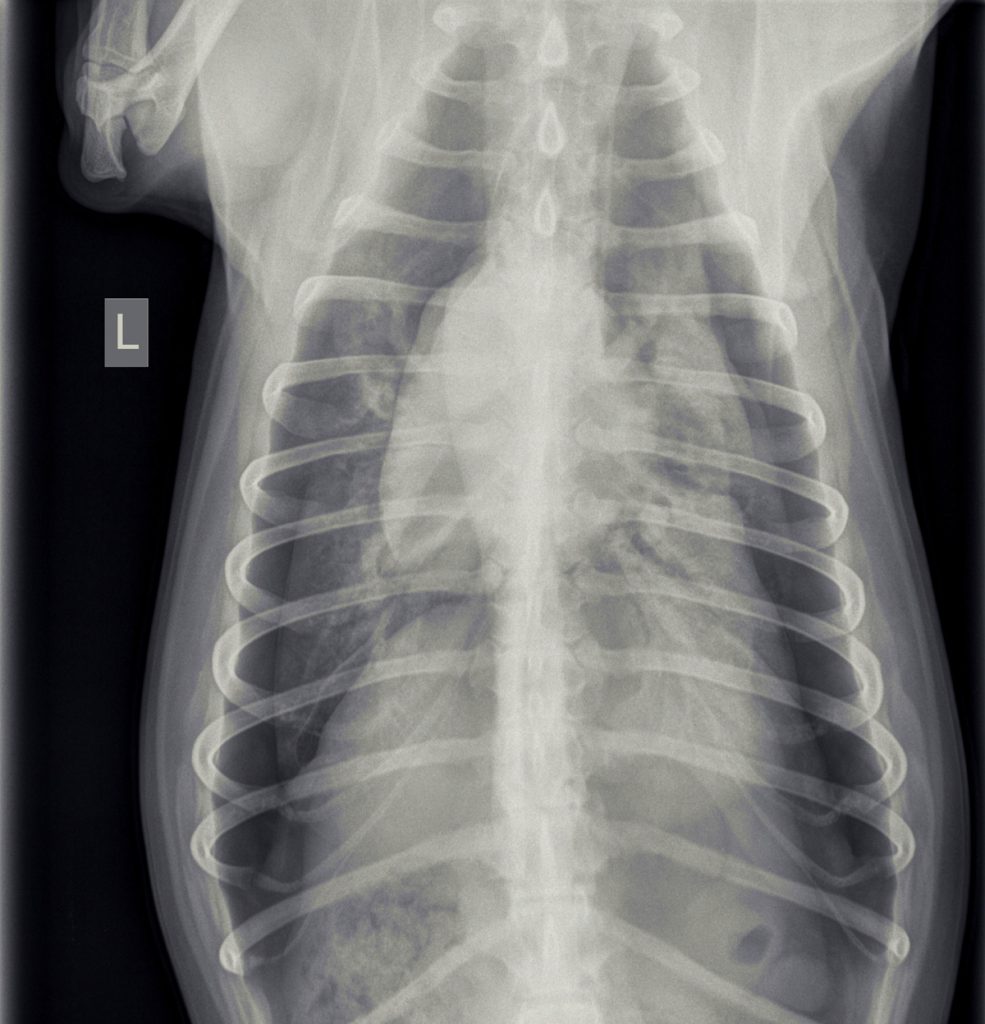

In overleg met de eigenaar van Jessie is besloten om röntgenfoto’s te maken.

Hierop was te zien dat er sprake was van een beiderzijdse klaplong. Dit betekent dat Jessie’s longen vrijwel geen lucht meer bevatten en ingeklapt in de borstholte lagen met lucht eromheen. Normaal hoort er geen lucht tussen de longen en de borstwand aanwezig te zijn.

De behandeling hiervan bestaat uit het plaatsen van een drain om de lucht die zich rondom de longen bevind af te zuigen. Hierdoor ontstaat er een vacuüm tussen de longen en de borstwand, waardoor de longen zich weer kunnen ontplooien. In de meeste gevallen is het nodig om de borstholte frequent af te zuigen. Wanneer de lucht productie na een paar dagen nog niet gestopt is, dan moet er gedacht worden aan operatief ingrijpen door een specialist.

Na overleg met de baasjes hebben we een drain geplaatst en zijn we begonnen met afzuigen van de lucht.

In de loop van de volgende dag werd de hoeveelheid lucht, die we konden afzuigen, steeds minder en ging het steeds beter met Jessie. Omdat het voor Jessie prettiger was, ging Jessie het einde van de dag naar huis. Jessie was enorm blij om haar baasje te zien en was eigenlijk wat te wild in de begroeting. Na 1,5 uur belde de eigenaar ons op, dat het niet goed ging, dus Jessie moest gelijk terugkomen. Jessie was weer erg kortademig. Dit was verbazend, gezien hoe goed het eigenlijk ging. We hebben nieuwe röntgenfoto’s gemaakt en zagen weer veel lucht. Mogelijk was er toch weer iets gaan lekken door de eerdere activiteit.